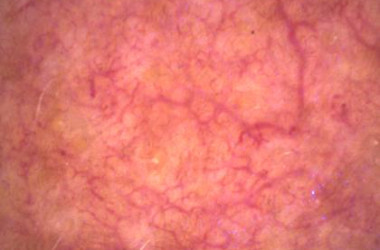

Opremljeno z vzporedno in navzkrižno polarizirano svetlobo:

- Vzporedno polarizirana svetloba vizualizira površinsko strukturo kože

- Navzkrižno polarizirana svetloba razkriva globlje plasti kože, kot so pigmentacija in vaskularne strukture

Načine osvetlitve lahko takoj spremenite s pritiskom na gumb kamere. Na podlagi zajetih slik programska oprema izvede enostavno in objektivno analizo slik gub, por in pigmentnih madežev. Popeljite svoje stranke na vizualno potovanje po obrazu in telesu.